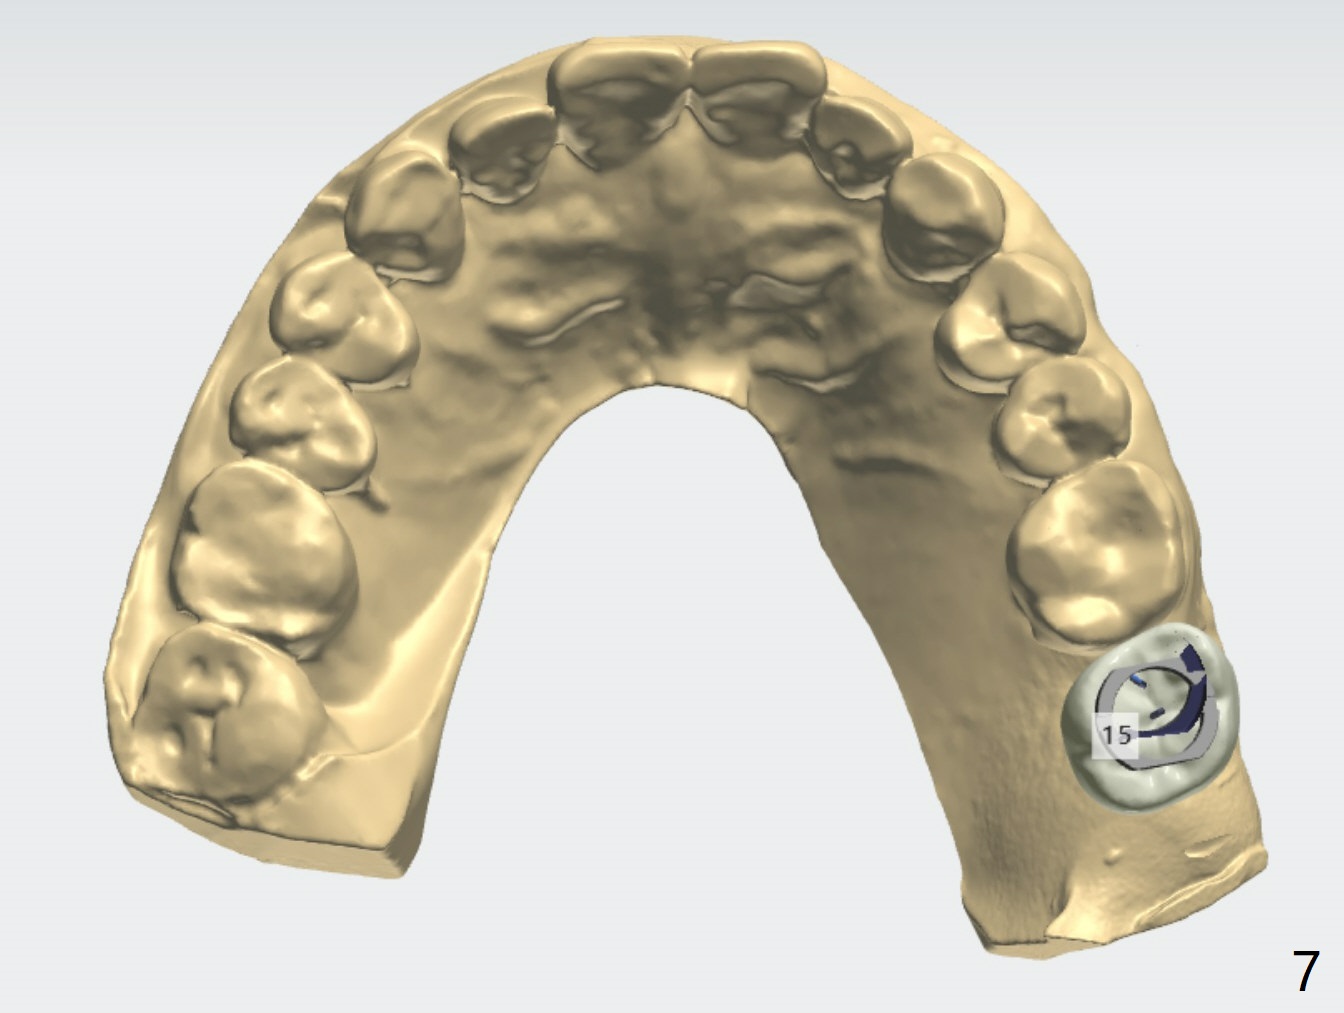

Short Implants

A 73-year-old woman

Xin Wei, DDS, PhD, MS 1st edition 03/15/2021, last revision 04/10/2021